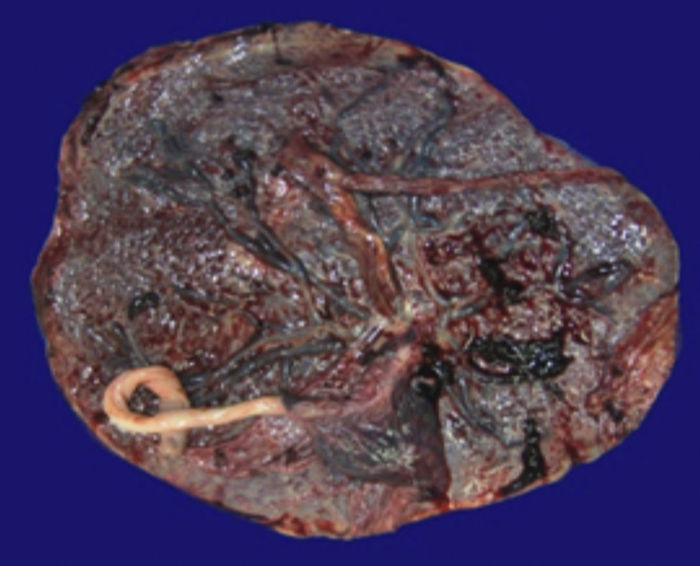

Se observa una pieza quirúrgica que corresponde al lóbulo superior del pulmón izquierdo. Pesó 80 g y presentaba una pleura opaca, despulida y congestiva. A los cortes seriados, se observaron numerosos quistes con un diámetro promedio entre 2 y 5 cm. Entre los quistes había áreas de parénquima pulmonar con congestión importante. Existe un quiste de mayor tamaño, con diámetro de 6 cm, cuya superficie interna es brillante y trabeculada (Figura 3). Otros quistes más pequeños estaban separados por tabiques de tejido conectivo, lo que se corroboró mediante la histología. La malformación estaba constituida por numerosos quistes revestidos por epitelio columnar y epitelio cilíndrico ciliado, que alternaban con algunas células mucosas. Estas células mucosas recuerdan las glándulas intestinales, mucoproductoras; entre estas se observaron tabiques de tejido fibroconectivo con algunas células comprimidas. Entre los quistes revestidos por este epitelio vemos, además, la presencia de músculo liso (Figura 4).

Figura 3 Fotografía macroscópica del lóbulo pulmonar superior izquierdo, que muestra numerosos quistes (el mayor de 6 cm de diámetro).